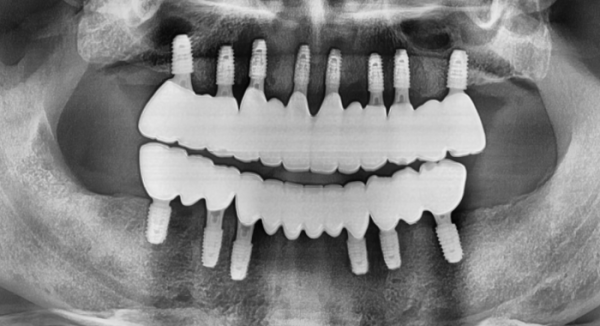

임플란트 전후사진